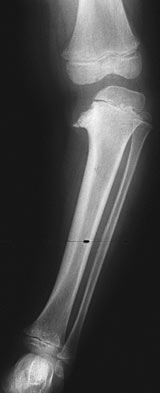

Identify the syndrome/disease

Infantile Blount's Disease

-Metaphyseal beaking